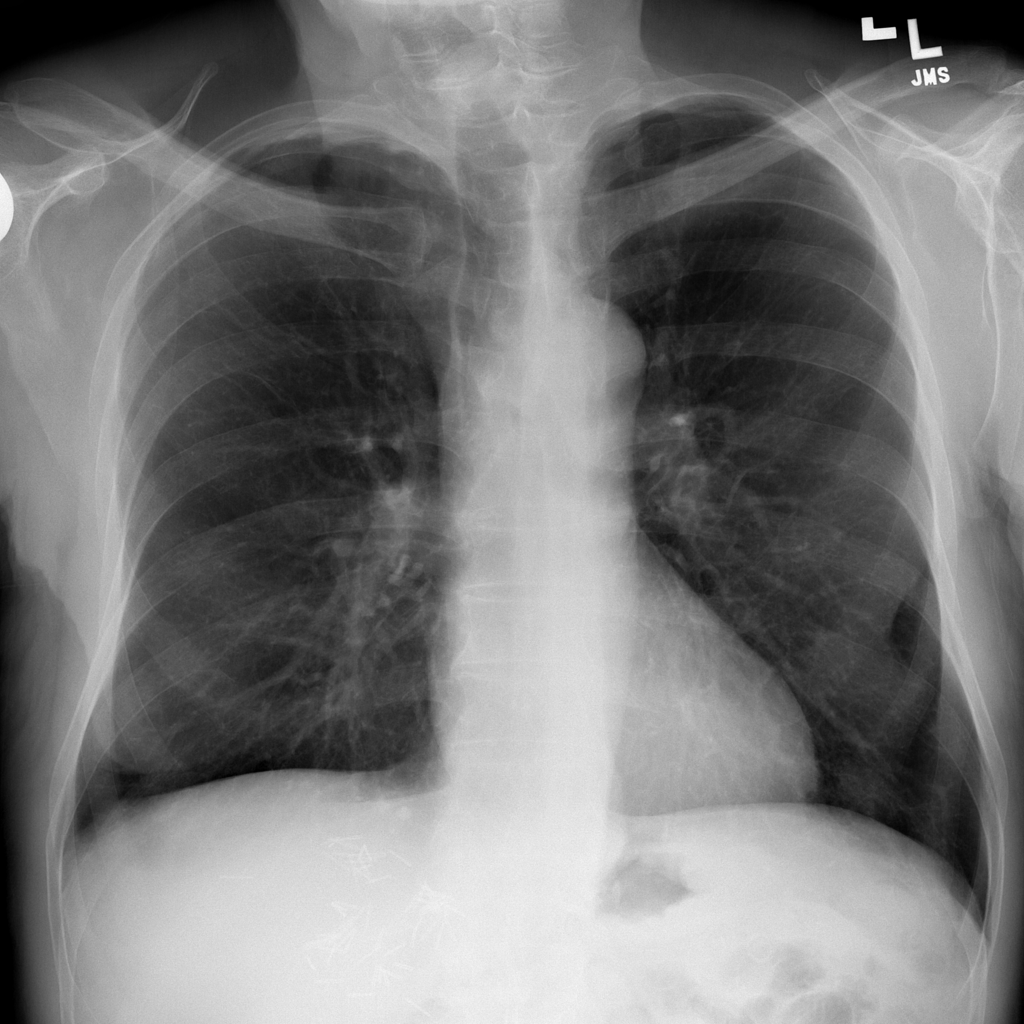

PAT-C255 · IMG-000Emphysema

PAT-C255 · IMG-000

PA